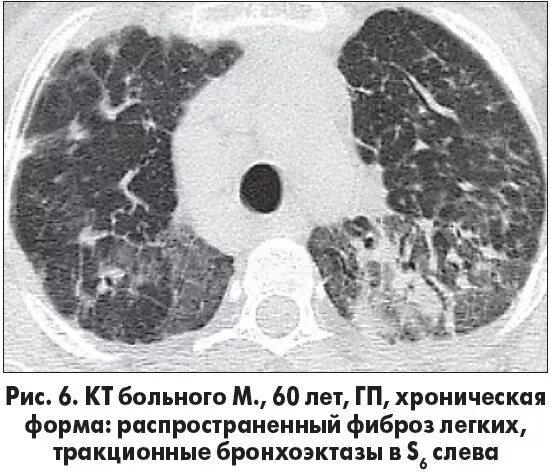

Пневмосклероз легких в пожилом возрасте лечение